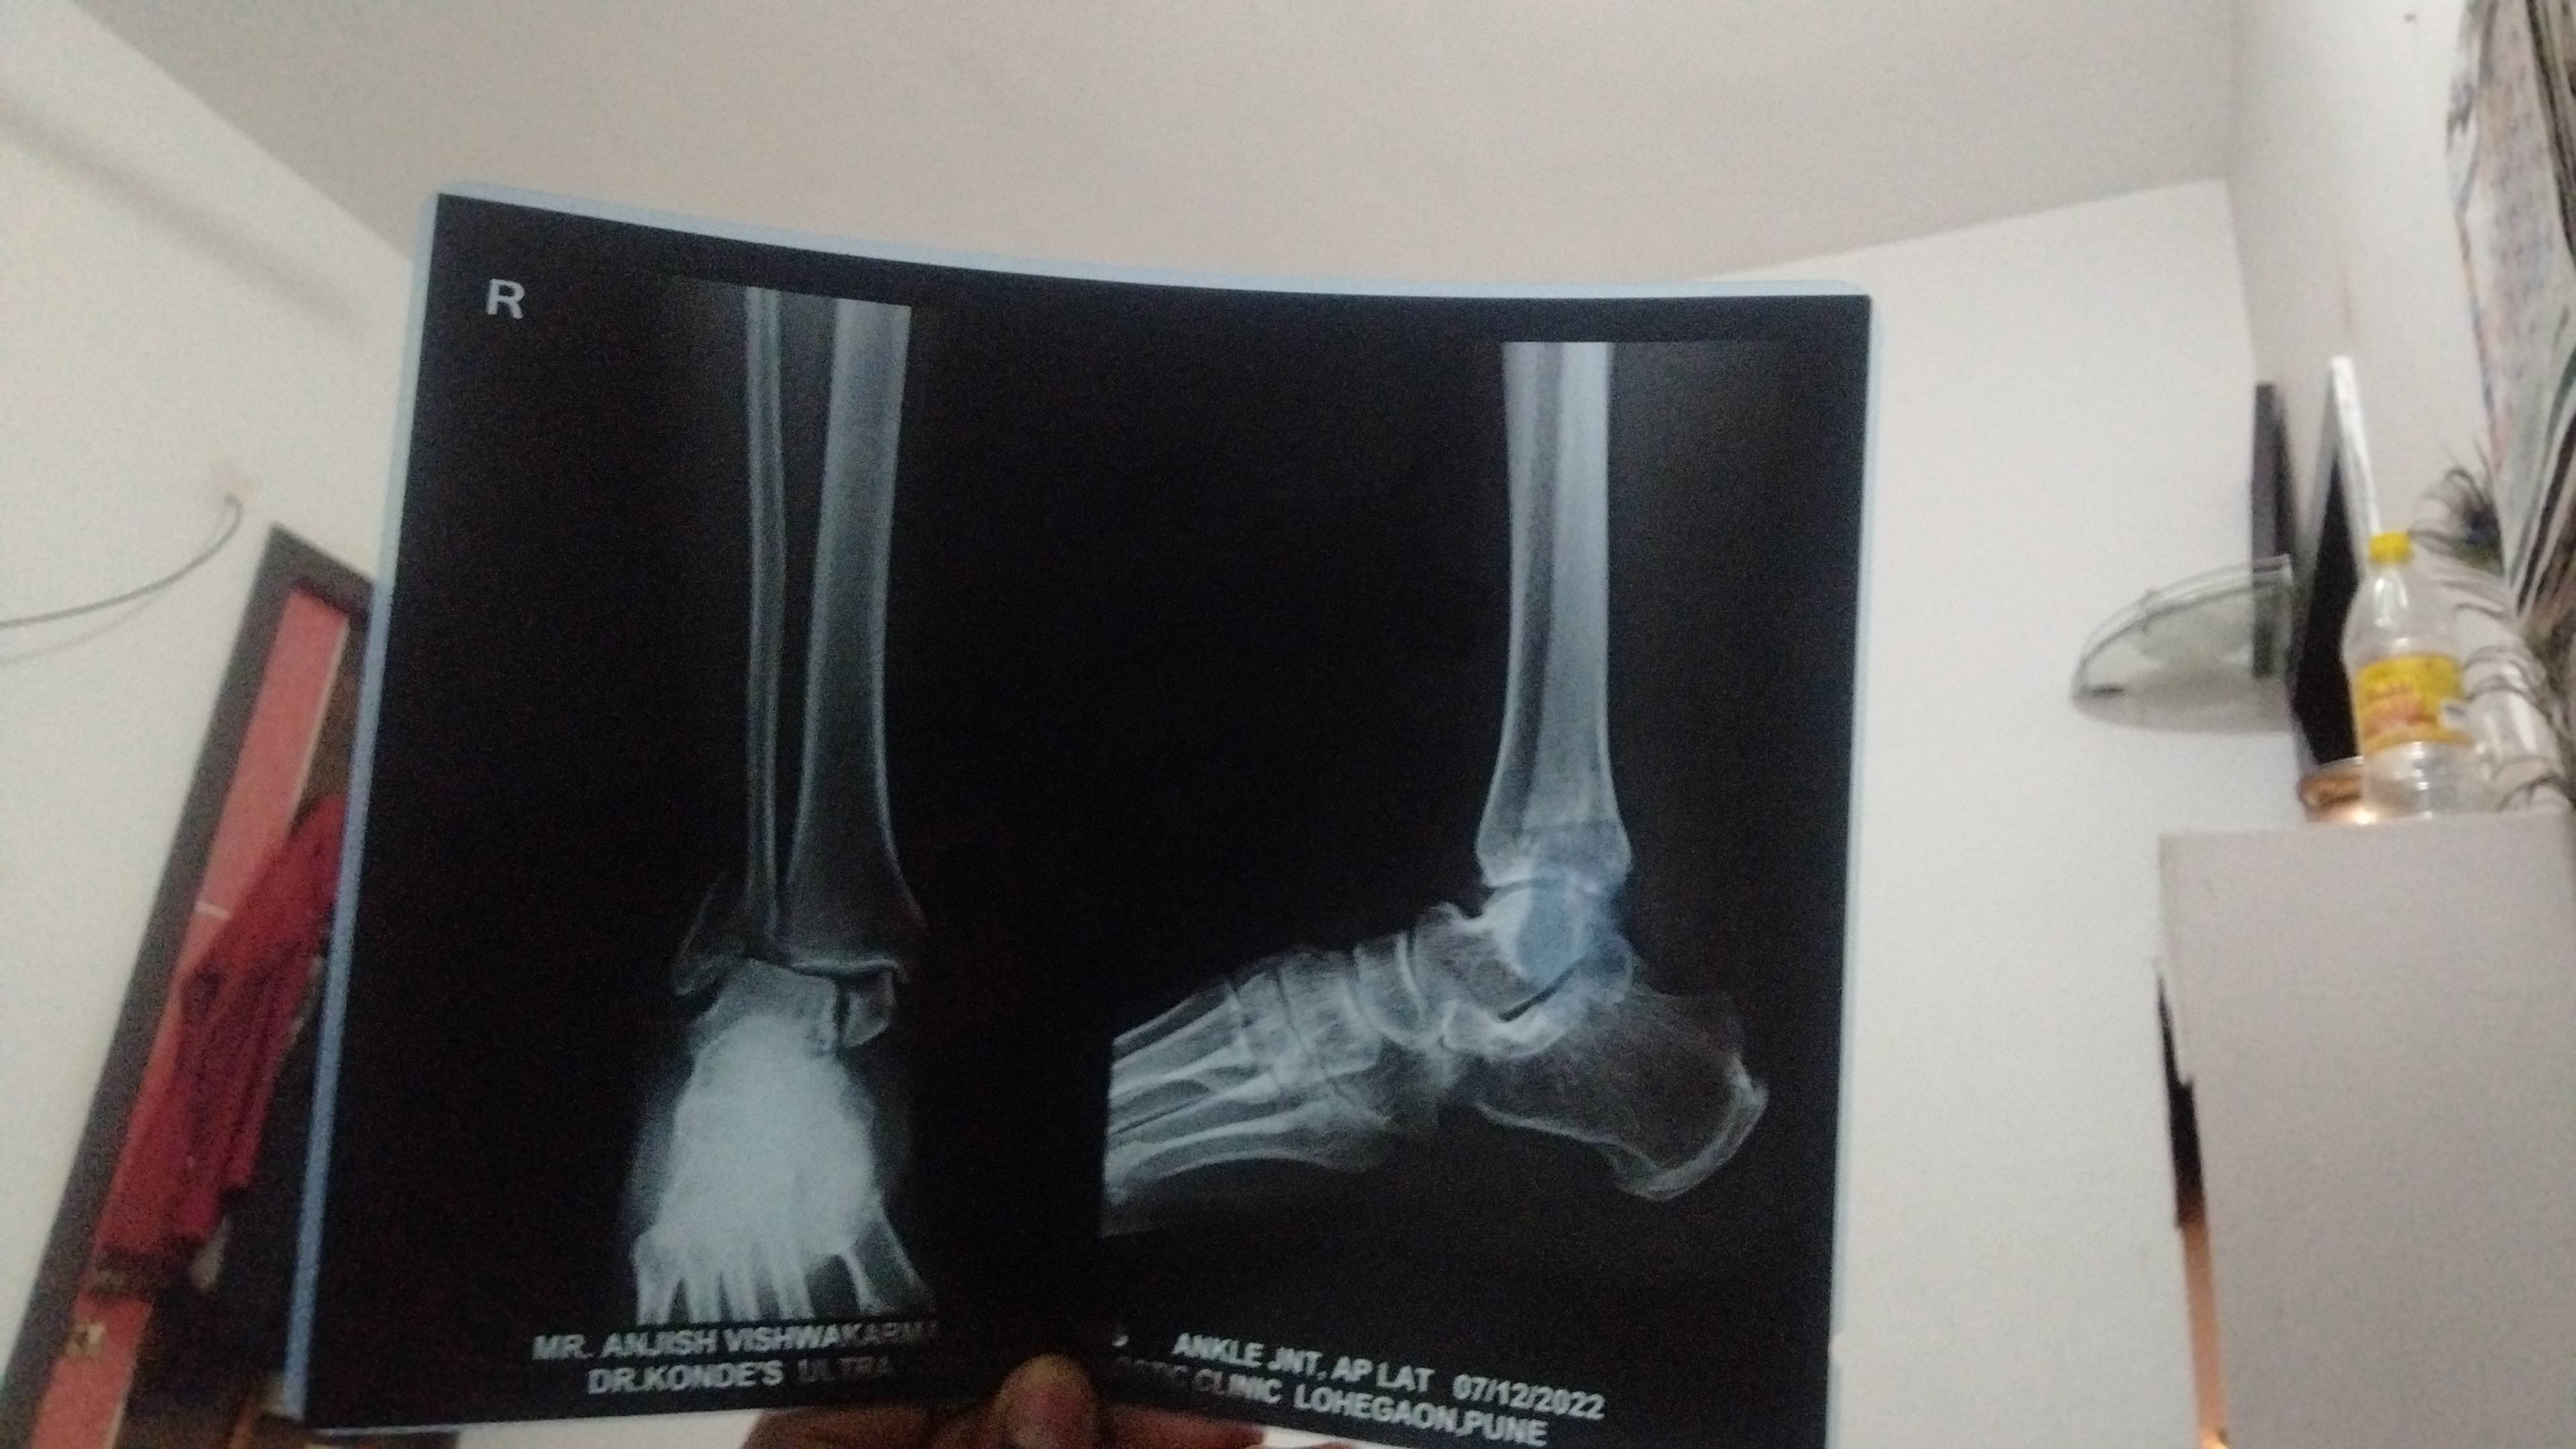

Pott fracture

Pott fracture does need operation